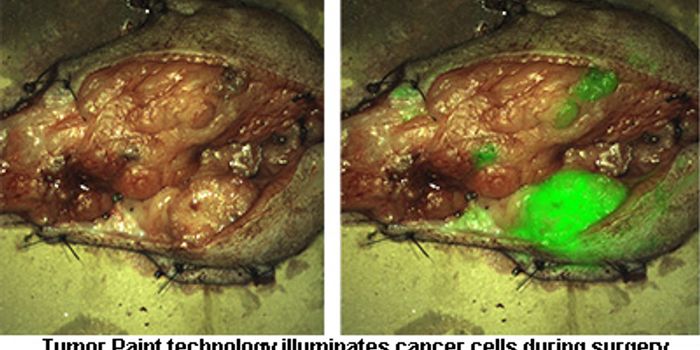

OCT 10, 2016Clinical & Molecular DXA new technique under Phase 1 clinical trial gave surgeons the ability to see a brain tumor glow like they’ve neve ...

NOV 02, 2015Clinical & Molecular DXIn the battle against cancer, scientists may be one step closer to detonating the tumor base camp, literally. The resear ...